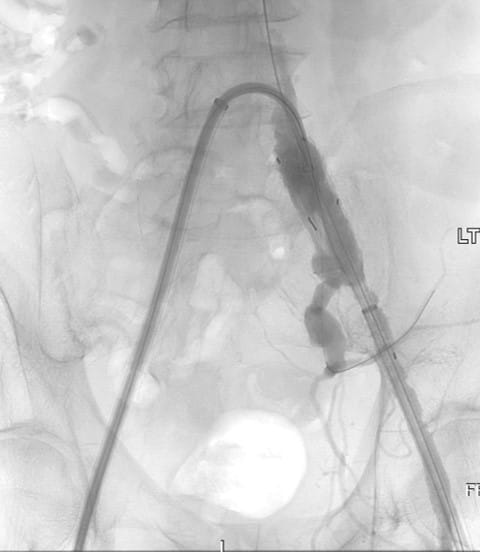

A 76-year-old male presented to UPMC for evaluation of aortoiliac aneurysm disease. His past medical history is also significant for mild emphysema, hyperlipidemia, lung and prostate cancer, and he has no family history of aneurysmal disease or connective tissue disorder. He is without symptoms of cardiac ischemia or peripheral claudication. His preoperative CT scan demonstrated the presence of a small infrarenal abdominal aortic aneurysm measuring 4.8cm, and bilateral large common iliac artery aneurysms, measuring 4cm and 3.8cm on the right and left, respectively. The internal iliac arteries were patent bilaterally (Figure 1 and 2). He underwent endovascular repair of his abdominal aortic aneurysm with placement of bilateral iliac branch endoprostheses (Gore Medical, Flagstaff AZ) for his bilateral common iliac artery aneurysms via percutaneous bilateral common femoral artery access (Figures 3-6). The patient tolerated the procedure well and was discharged on post-operative day two.

Figure 4: Positioning of the left iliac branch endoprosthesis with cannulation of the internal iliac limb